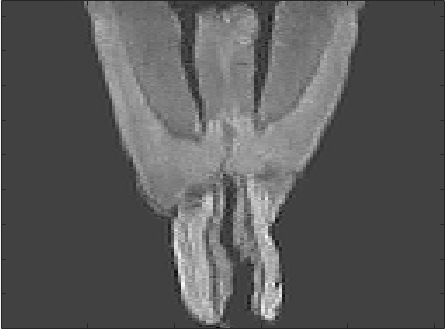

We present results for a histological serial sectioning of a sectioned mouse brain, data courtesy of Oliver Schmitt. For results on DCE-MRI data we refer to [2]. Fig. 1 shows results for a sequential linear pre-registration, the new based registration, and a standard sequential based registration as a reference (robust and fast to compute).

Although only one iteration was performed for the sequential registration, the computing time is about six times as for the approach. The result also shows a much stronger spatial correlation, indicating that the sequential approach has not yet converged.